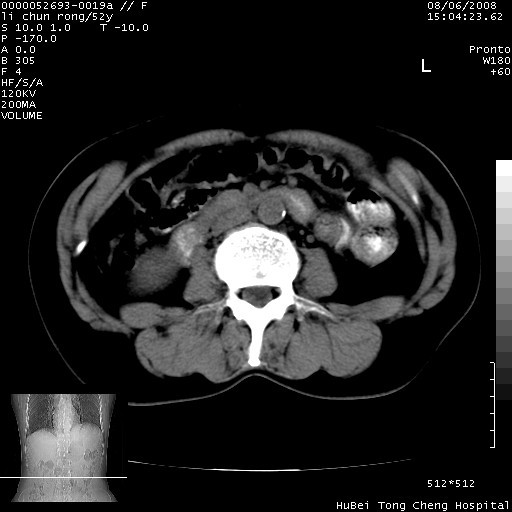

以下是引用云翔在2008-8-7 6:20:00的发言:[br]胰尾部囊性病变,考虑假囊肿,结合实验室检查疾病史

以下是引用zjzjr在2008-8-7 8:38:00的发言:[br]支持胰腺炎伴假囊肿形成,左肾小囊肿.少量腹水.

以下是引用随光逐影在2008-8-7 9:12:00的发言:[br]1)考虑胰腺炎伴假性囊肿形成可能性大;胰腺囊腺瘤待排。2)左肾小囊肿。3)少量腹水。